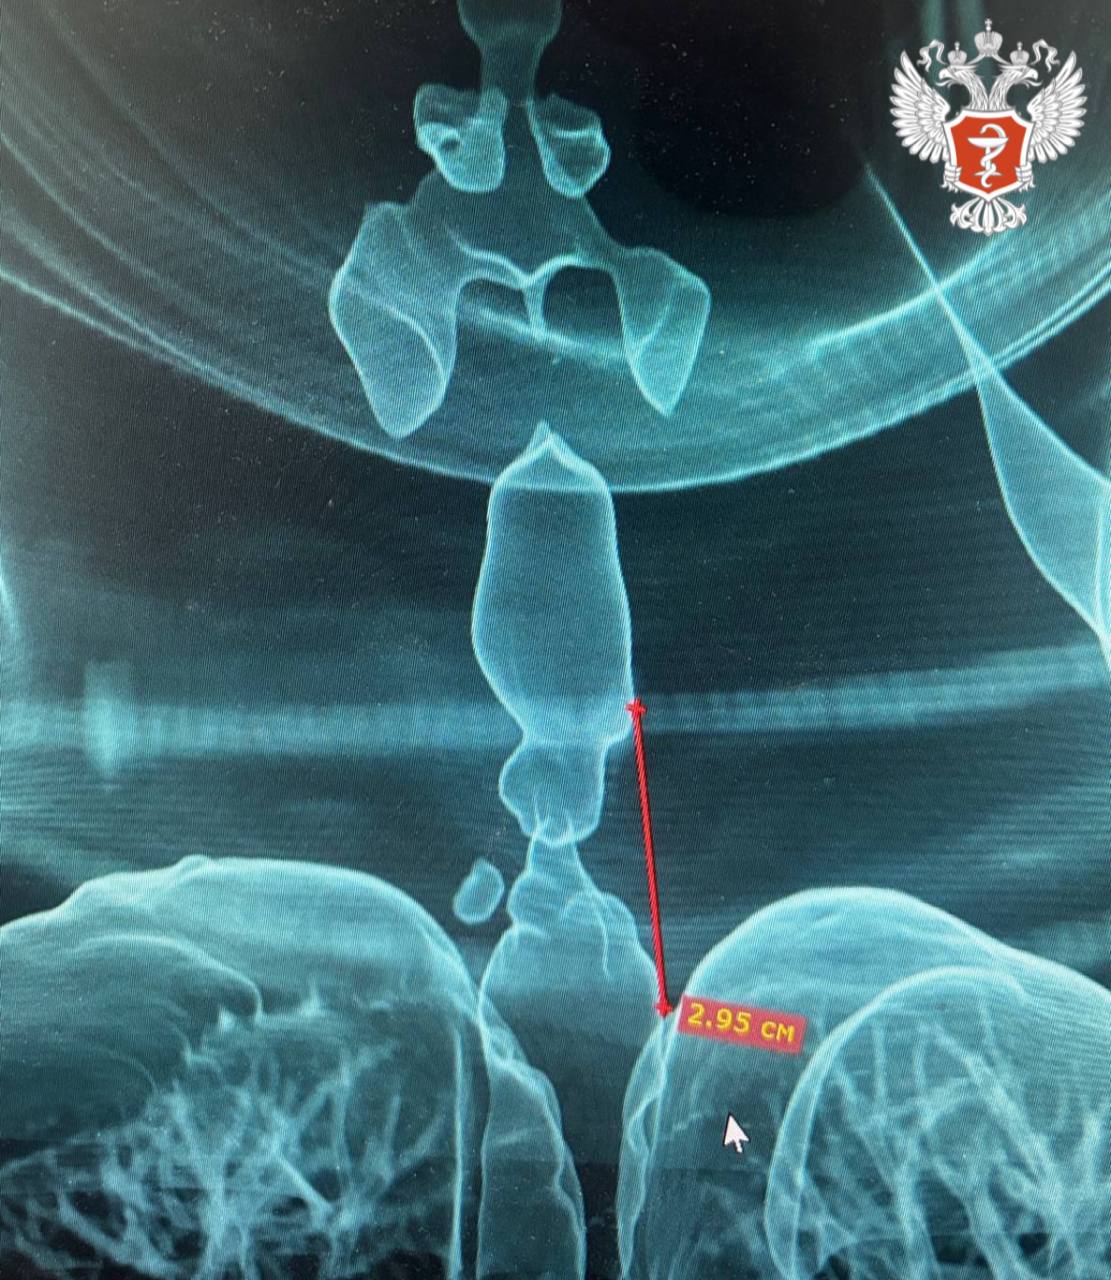

Чтобы получить более точную оценку протяжённости и расположения сужения, специалисты Городской клинической больницы №9 создали 3D-модель дыхательных путей пациентки.

Протяженность стеноза составила 2,95 см, а минимальный просвет трахеи — всего 5 мм. Такая ситуация угрожала жизни пациентки и требовала проведения срочной операции.